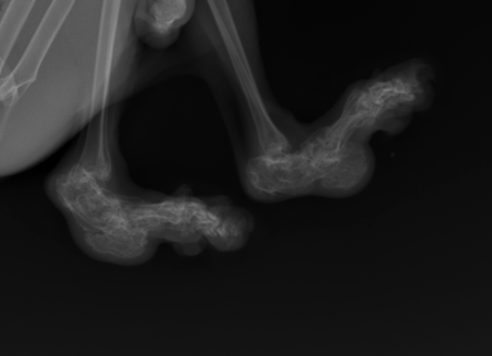

Опытный специалист выявляет патологию в ходе внимательного осмотра и изучения рентгеновских снимков, показывающих отклонения в строении костей позвоночника, лап и хвоста.

Остеохондродисплазия шотландских вислоухих кошек

В результате может развиться тяжелое заболевание — остеохондродисплазия.